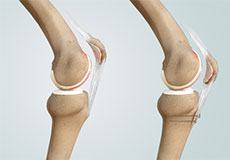

Knee Osteotomy

Knee osteotomy is a surgical procedure in which the upper shinbone (tibia) or lower thighbone (femur) is cut and realigned. It is usually performed in arthritic conditions affecting only one side of your knee.

High Tibial Osteotomy

High tibial osteotomy is a surgical procedure performed to relieve pressure on the damaged site of an arthritic knee joint. It is usually performed in arthritic conditions affecting only one side of your knee and the aim is to take pressure off the damaged area and shift it to the other side of your knee with healthy cartilage.